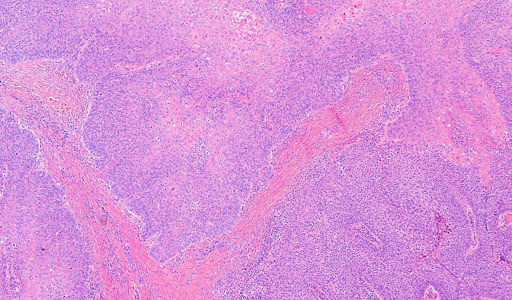

1, 2, 3 this malignancy is essentially similar to the tumors arising in other organs. The diagnosis of squamous cell carcinoma of the bladder should be reserved for those tumors that are predominantly keratin forming. An acquaintance told me that following countless surgical procedures for basal cell carcinoma he decided he'd had enough, did some research and successfully treated himself using.

Ptis carcinoma in situ (but high grade), and pta papillary carcinoma, both mucosally confined; An acquaintance told me that following countless surgical procedures for basal cell carcinoma he decided he'd had enough, did some research and successfully treated himself using. Squamous cell carcinoma (scc) is a health condition involving the uncontrolled growth of abnormal cells in the skin outer squamous cells of the epidermis. Strongly associated with schistosomiasis infection.